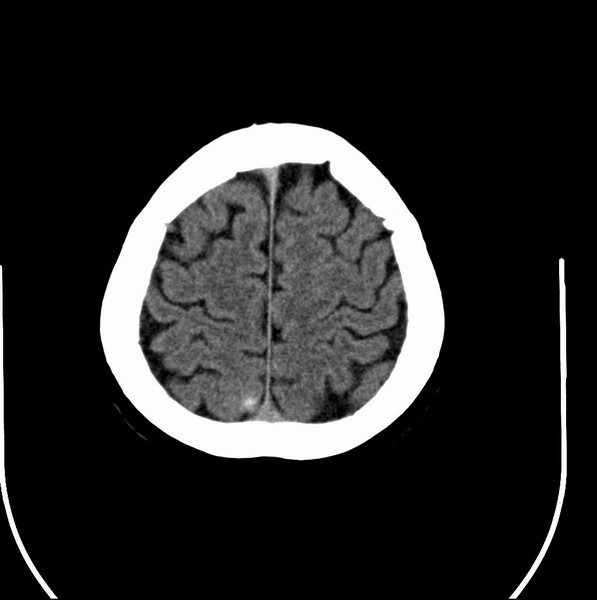

以下是引用余辉在2009-4-25 10:34:00的发言:[br]上矢状窦旁软组织肿块,内有钙化,与上矢状窦边界不清,灶后颅骨内板骨质增生硬化,支持考虑脑膜瘤,建议增强

以下是引用hmyj9在2009-4-25 14:21:00的发言:[br]病灶紧贴颅板处,中心高密度周围见软组织密度,局部颅板有增生,支持脑膜瘤诊断,建议增强。

以下是引用边生丽在2009-4-25 11:55:00的发言:[br][br] [br] 考虑脑膜瘤可能性大;建议行进一步检查。 [br] [br] [br]